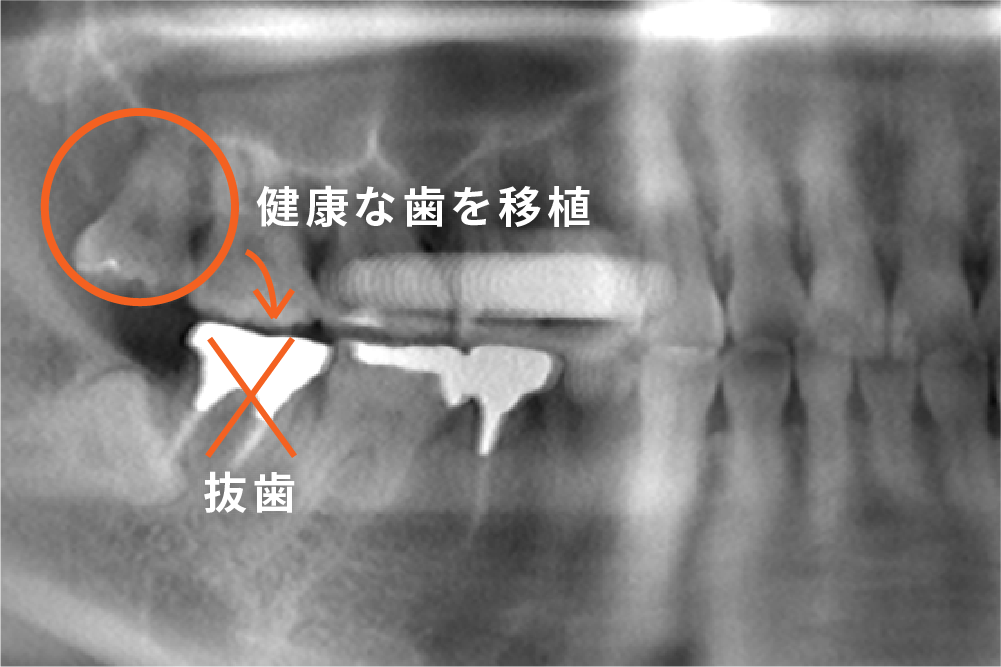

生え方によって腫れや痛みだけでなく、虫歯や歯並びへの悪影響を及ぼすことがあります。特に、横向きや斜めに生えている場合は、周囲の歯や歯ぐきのトラブルを引き起こしやすいため、早めのレントゲン診断と定期的なチェックが大切です。

その結果、虫歯や歯周病のリスクが高まり、さらに隣の歯の根を圧迫して歯根が溶けてしまう「外部吸収」などのトラブルを起こすこともあります。